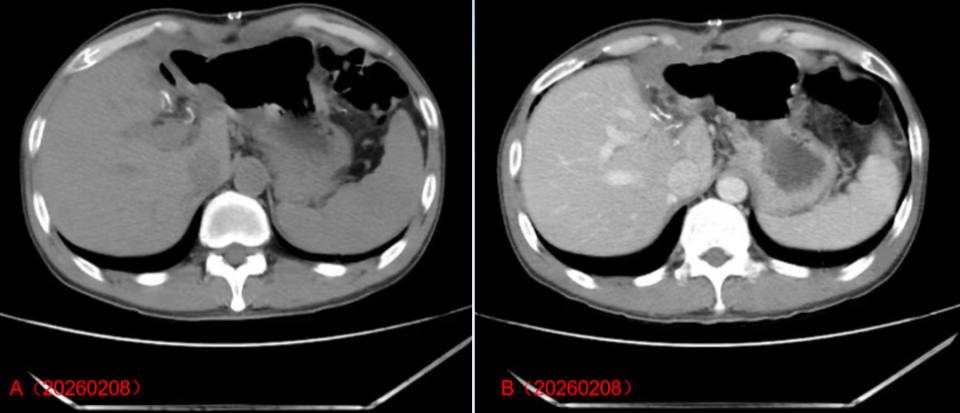

术后于2026年2月3日行薄层CT平扫检查,显示肝左叶切除术后改变,术区炎性渗出性改变。2026年2月8日再次复查薄层CT平扫,显示肝左叶切除术后改变,术区炎性渗出性改变较前吸收减少。术后患者恢复情况尚可,复查肝功能等正常,病情明显好转后出院,于2026年2月9日出院,并继续院外规律采用“ETV 1 mg、仑伐替尼”治疗。

HCC患者肝脏手术后的影像学特征

注:图A、B是术后2026年2月8日CT增强影像,显示:肝左叶切除术后,切缘多发结节状、条状致密影,术区脂肪间隙模糊、见斑片状低密度影,增强扫描未见异常强化灶。提示肝左叶切除术后改变,术区炎性渗出性改变,右侧腹壁软组织肿胀。